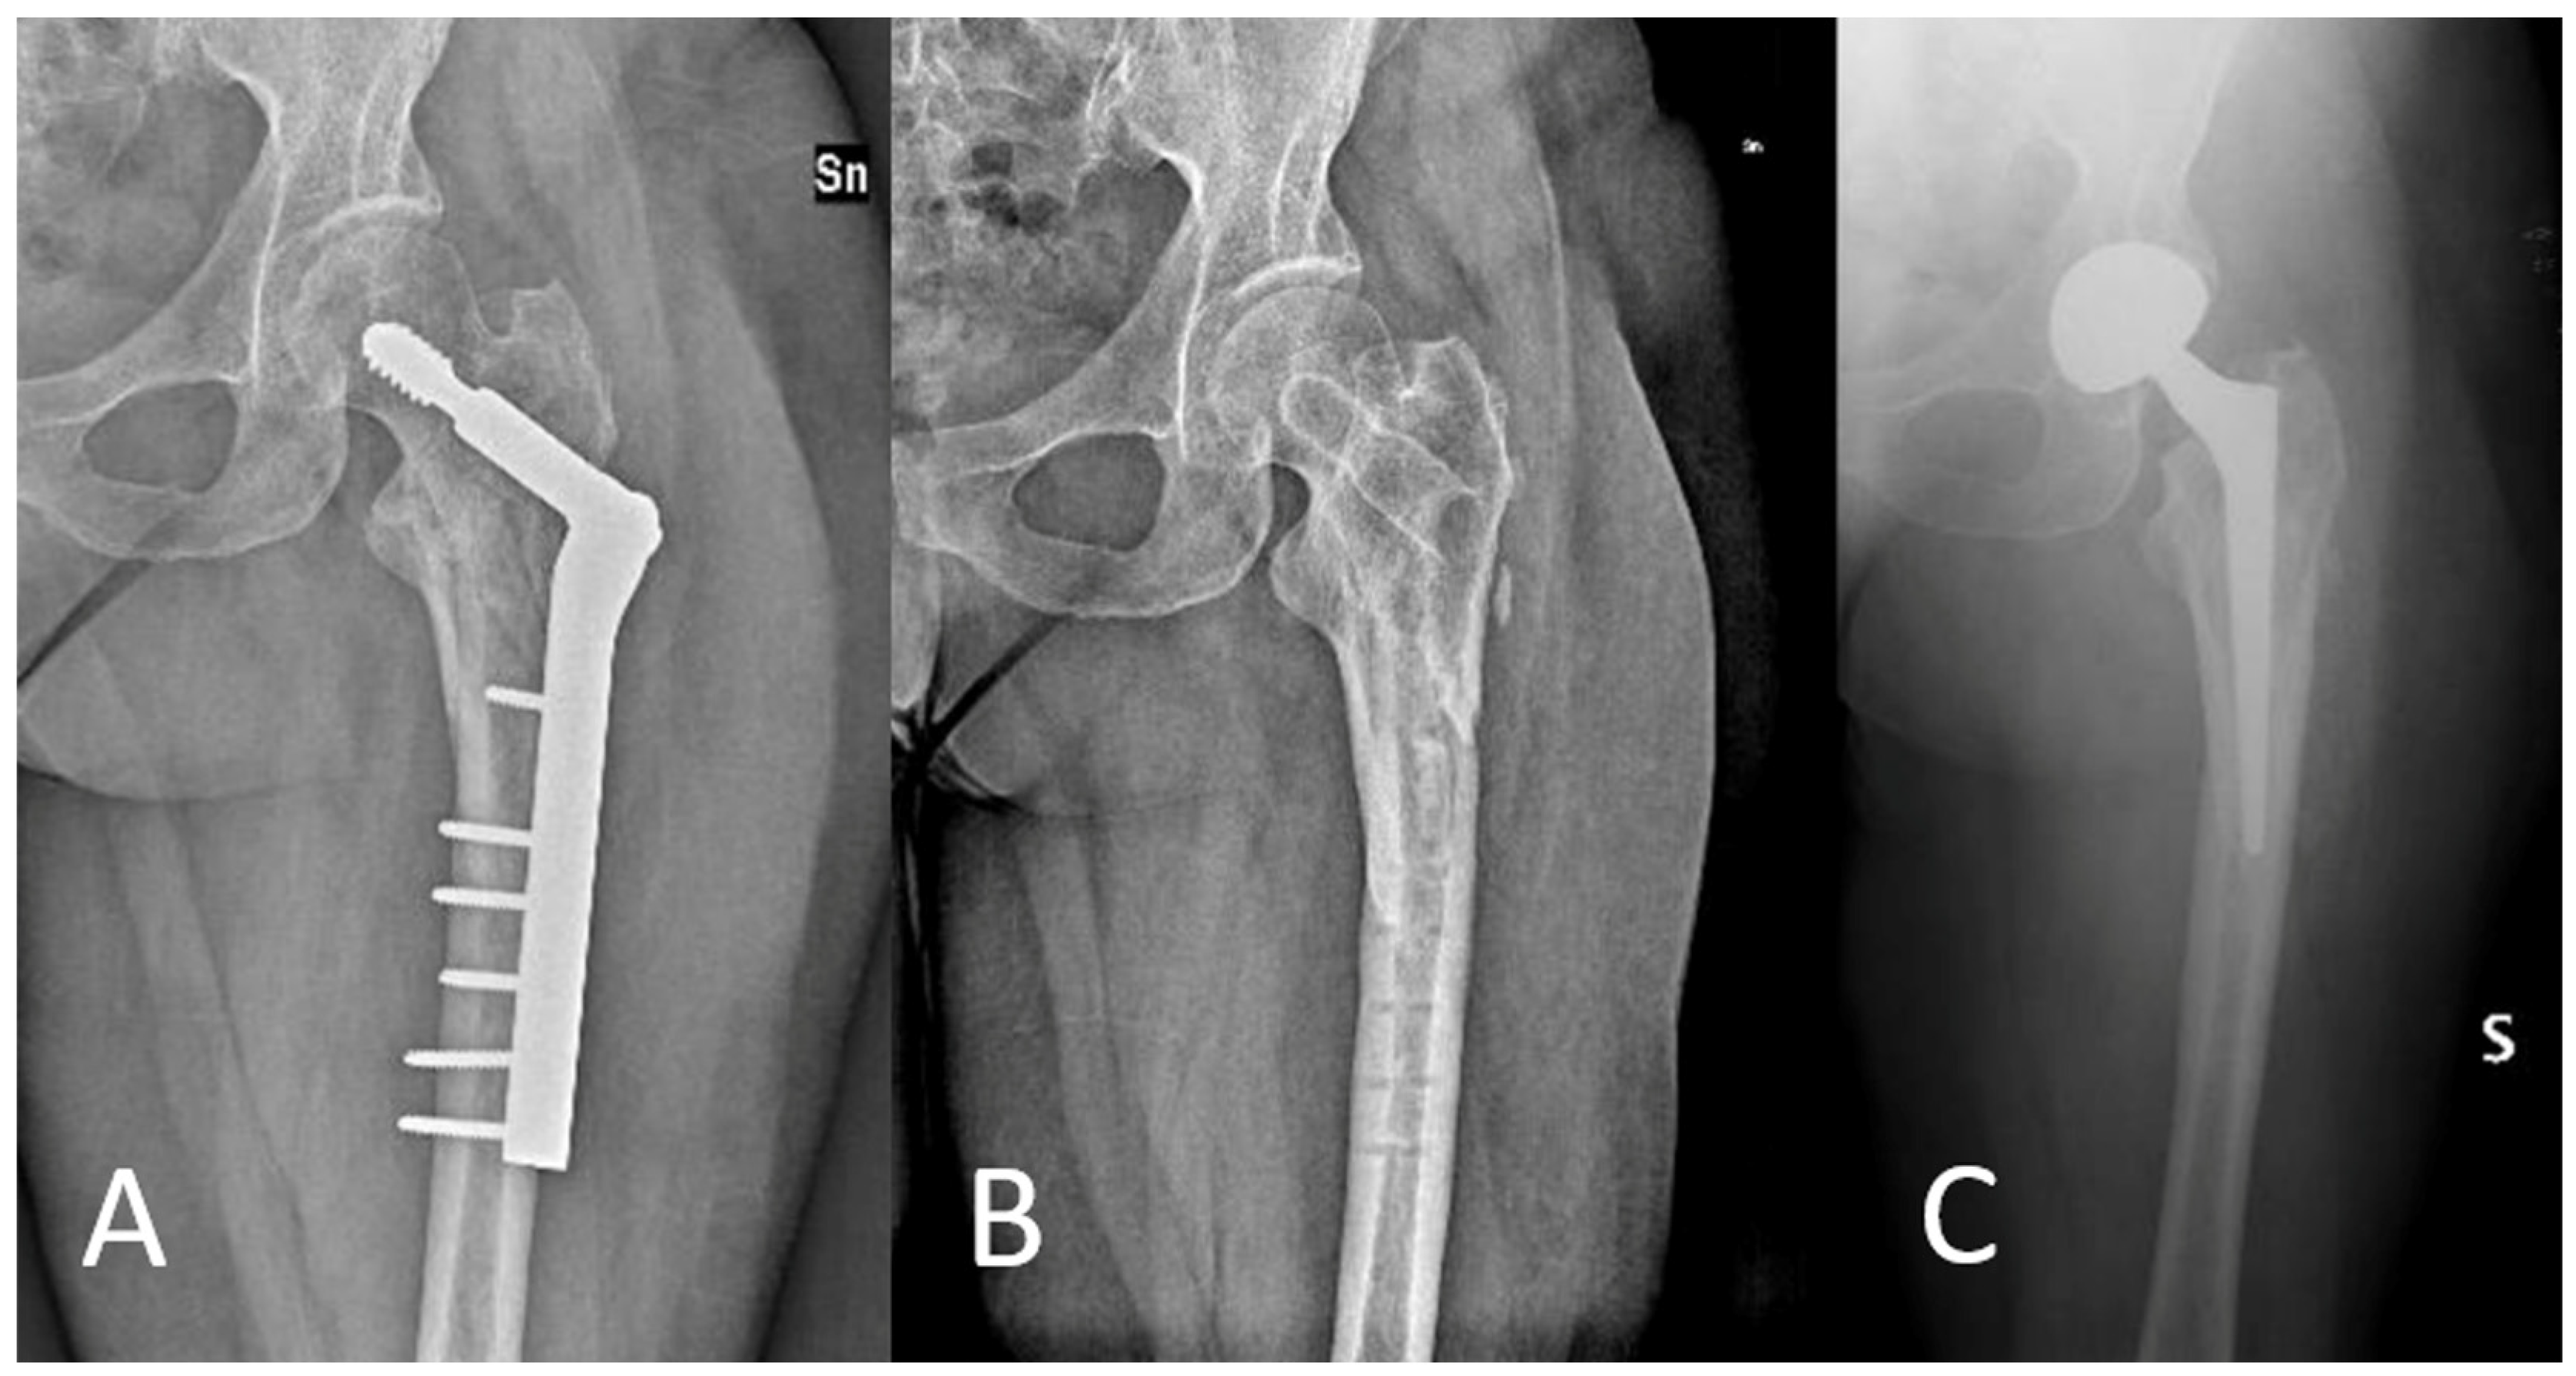

Angle-Adjustable Dynamic Hip Screw Plate for Unstable Trochanteric Fractures in Middle-Aged Patients: Mid-Term Outcomes and Return to Sport

2.1. Surgical Technique

4. Discussion